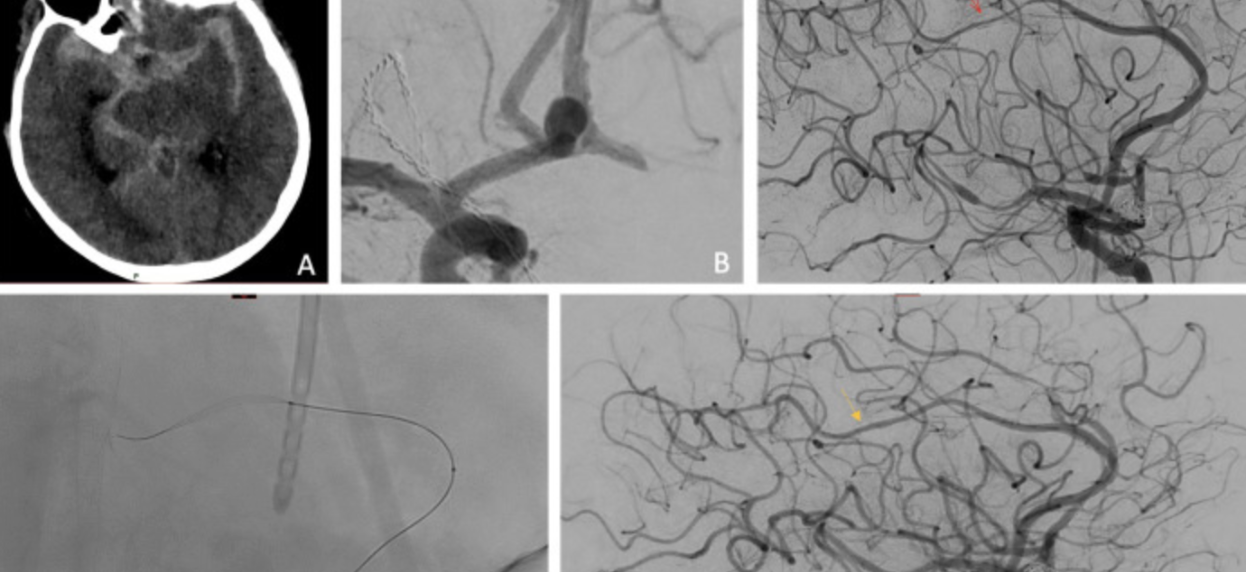

Challenging the limits of angioplasty: Comaneci device for distal vasospasm following subarachnoid hemorrhage

Long-term outcomes of temporary stent-assisted coil embolization for the treatment of intracranial aneurysms using Comaneci remodeling device

Jakub Onikijuk, MD et al.

Download PDF - 11/25 Challenging the limits of angioplasty: Comaneci device for distal vasospasm following subarachnoid hemorrhage Download PDF

- 10/24 Sustained efficacy of angioplasty for cerebral vasospasm … device comparison DOI: 10.1016/j.jocn.2024.110784

- 10/24 Treatment of Cerebral Vasospasm … Comaneci DOI: 10.5334/jbsr.3714

- 11/22 Comaneci-assisted coiling of wide-necked intracranial Aneurysm: Single center preliminary experience Journal of Clinical Medicine

- 8/22 COMMANd: multicenter experience 10.1136/neurintsurg-2022-019272

- 5/22 Distal cerebral vasospasm treatment … Comaneci 10.1136/neurintsurg-2022-018699

- 5/21 Early Experience with Comaneci … FDA-Approved 10.1159/000514371

- 2/21 Comaneci Device for Temporary Coiling Assistance … 10.1016/j.wneu.2021.02.080

- 10/20 Comaneci device-assisted embolization … unfavorable ratio 10.1186/s12883-020-01963-2

- 7/20 Treatment of cerebral vasospasm … subarachnoid hemorrhage … PMID: 32722988 DOI: 10.1177/1591019920945554

- 5/20 Comaneci-Assisted Coiling as a Treatment Option … Neurosurgery, nyaa200, 10.1093/neuros/nyaa200

- 2/20 Neck-bridging device for endovascular coiling of wide-necked MCA aneurysm http://dx.doi.org/10.1136/neurintsurg-2019-015639